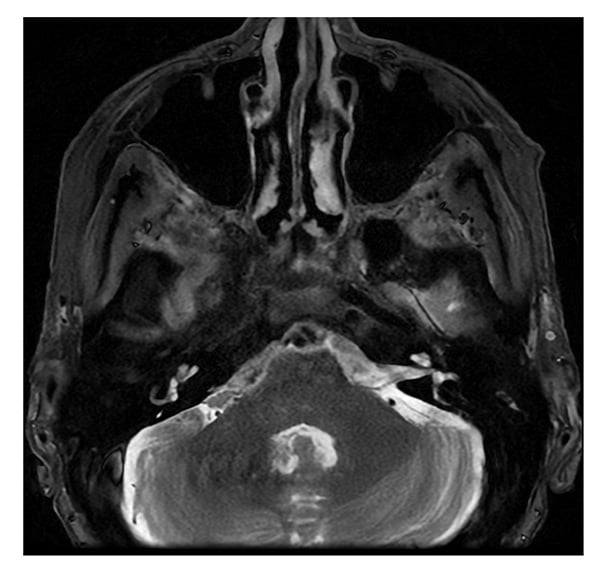

Magnetic resonance imaging (MRI) of the orbit and brain (Figures 1 and 2) revealed mild soft-tissue fullness surrounding the frontal branches of both superficial temporal arteries, suggestive of temporal arteritis. Marked superficial enhancement with fullness of the intraorbital segments of both optic nerves with surrounding fat reticulation was consistent with optic perineuritis. Serologic testing for tuberculosis, syphilis, sarcoidosis, immunoglobulin G4 (IgG4)-related disease, and monoclonal gammopathy was unremarkable.

Figure 1: MRI of the brain shows slight soft-tissue fullness surrounding the right greater than left frontal branches of the superficial temporal arteries.